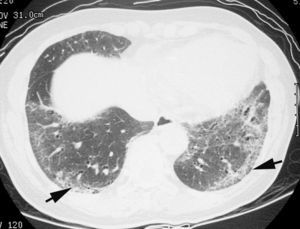

En algunos casos de NINE, como suele suceder en otras neumonías intersticiales, la radiografía de tórax es normal27,28. En la TCAR, lo que caracteriza al patrón de NINE es el «vidrio deslustrado» periférico, en las zonas medias y basales de ambos pulmones (fig. 8)29,30. La panalización ocurre en el 27% de los pacientes, y a medida que progresa la fibrosis, las bronquiectasias y bronquiolectasias de tracción son más visibles7,31. Los hallazgos radiológicos pueden desaparecer por completo tras el tratamiento con esteroides.